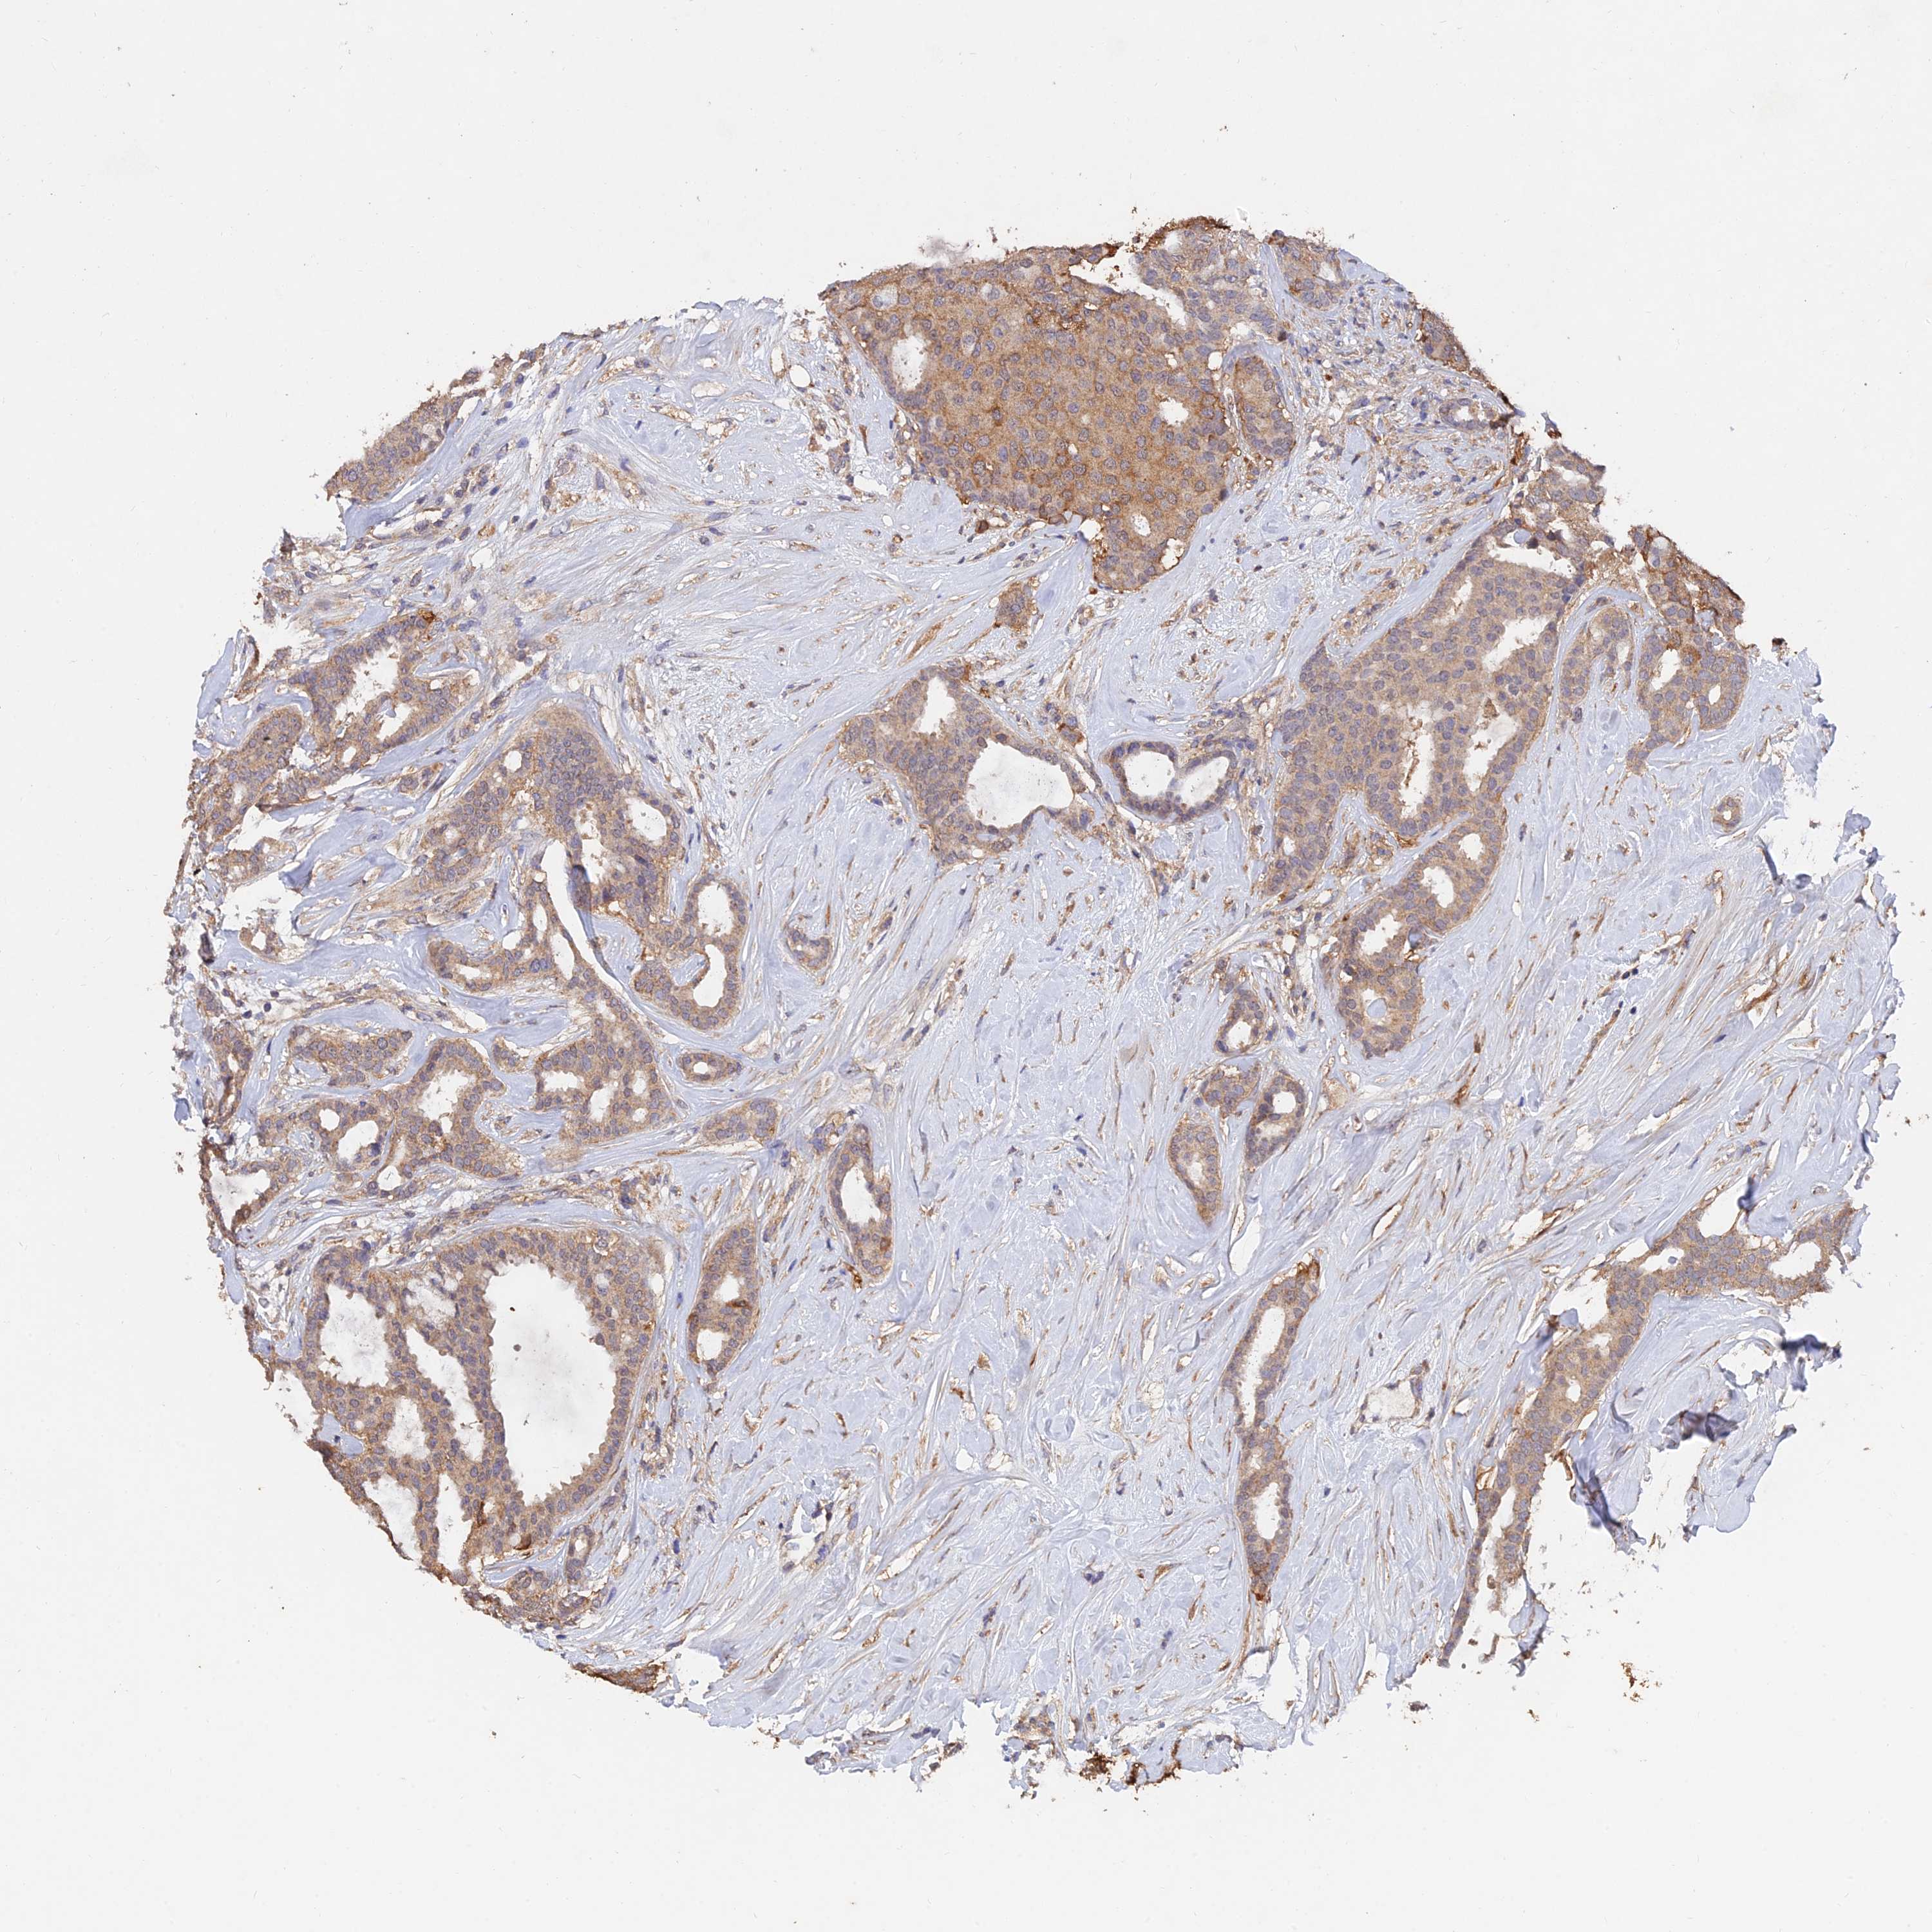

CANCER BREAST CANCER Show tissue menu

BRCA TCGA BRCA VALIDATION PROTEIN EXPRESSION

Breast cancer

Human cancer